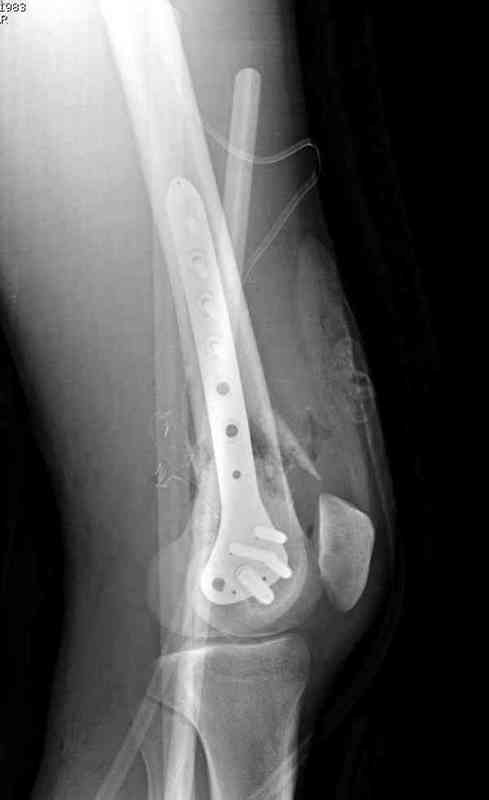

I have a similair case who had non -union after supracondylar nail, which broke at the fracture site. I had to take the nail out and then fixed it with LISS_DF (locking plate) I did use the bone graft. fracture healed with 3 months.

If fixation is solid fracture unite very well provided the environment of the fracture is suitable.